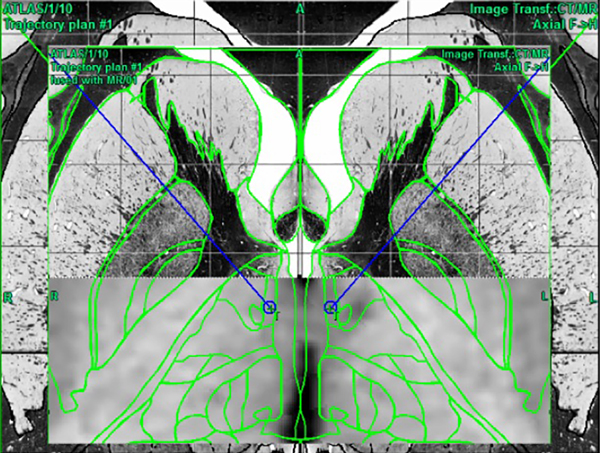

Figura 1. Planeamiento quirúrgico mediante software Praezis AG 3A plus para identificar hipotálamo posteromedial usando el atlas de estereotaxia de Schaltenbrand y Wahren.10

En todos los casos y previo a la introducción del electrodo de radiofrecuencia, las trayectorias se ajustaron de acuerdo a las imágenes de tomografía contrastada para evitar la lesión de vasos o la entrada al ventrículo.(Figura 1)

Figura 1. Planeamiento quirúrgico mediante software Praezis AG 3A plus para identificar hipotálamo posteromedial usando el atlas de estereotaxia de Schaltenbrand y Wahren.10